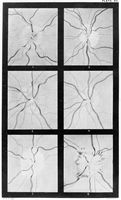

Reproductions of six ophthalmoscope images: figures 1 & 2: unilateral optical neuritis, probably cerebral syphiloma (right normal); figures 3 & 4: chronic optic neuritis in epileptoid convulsions; figure 5: slight optic neuritis in anaemia; figure 6: optic neuritis in lead poisoning. Published in Gowers, W. R.: A manual and atlas of medical ophthalmoscopy, London : J. & A. Churchill, 1879. Related images: M0019102, M0019103, M0019105, M0019106

1 photograph glass plate negative; 8.3 x 10.8 cm